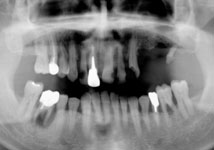

長年放置したために歯周病が進行し、尚且つ入れ歯が噛みにくくなったと受診され、両サイドの奥にインプラントを入れ全顎的な治療を行い審美改善しました。

今は見た目もよくなり、よく噛めるようになったと喜んでいらっしゃいます。 |